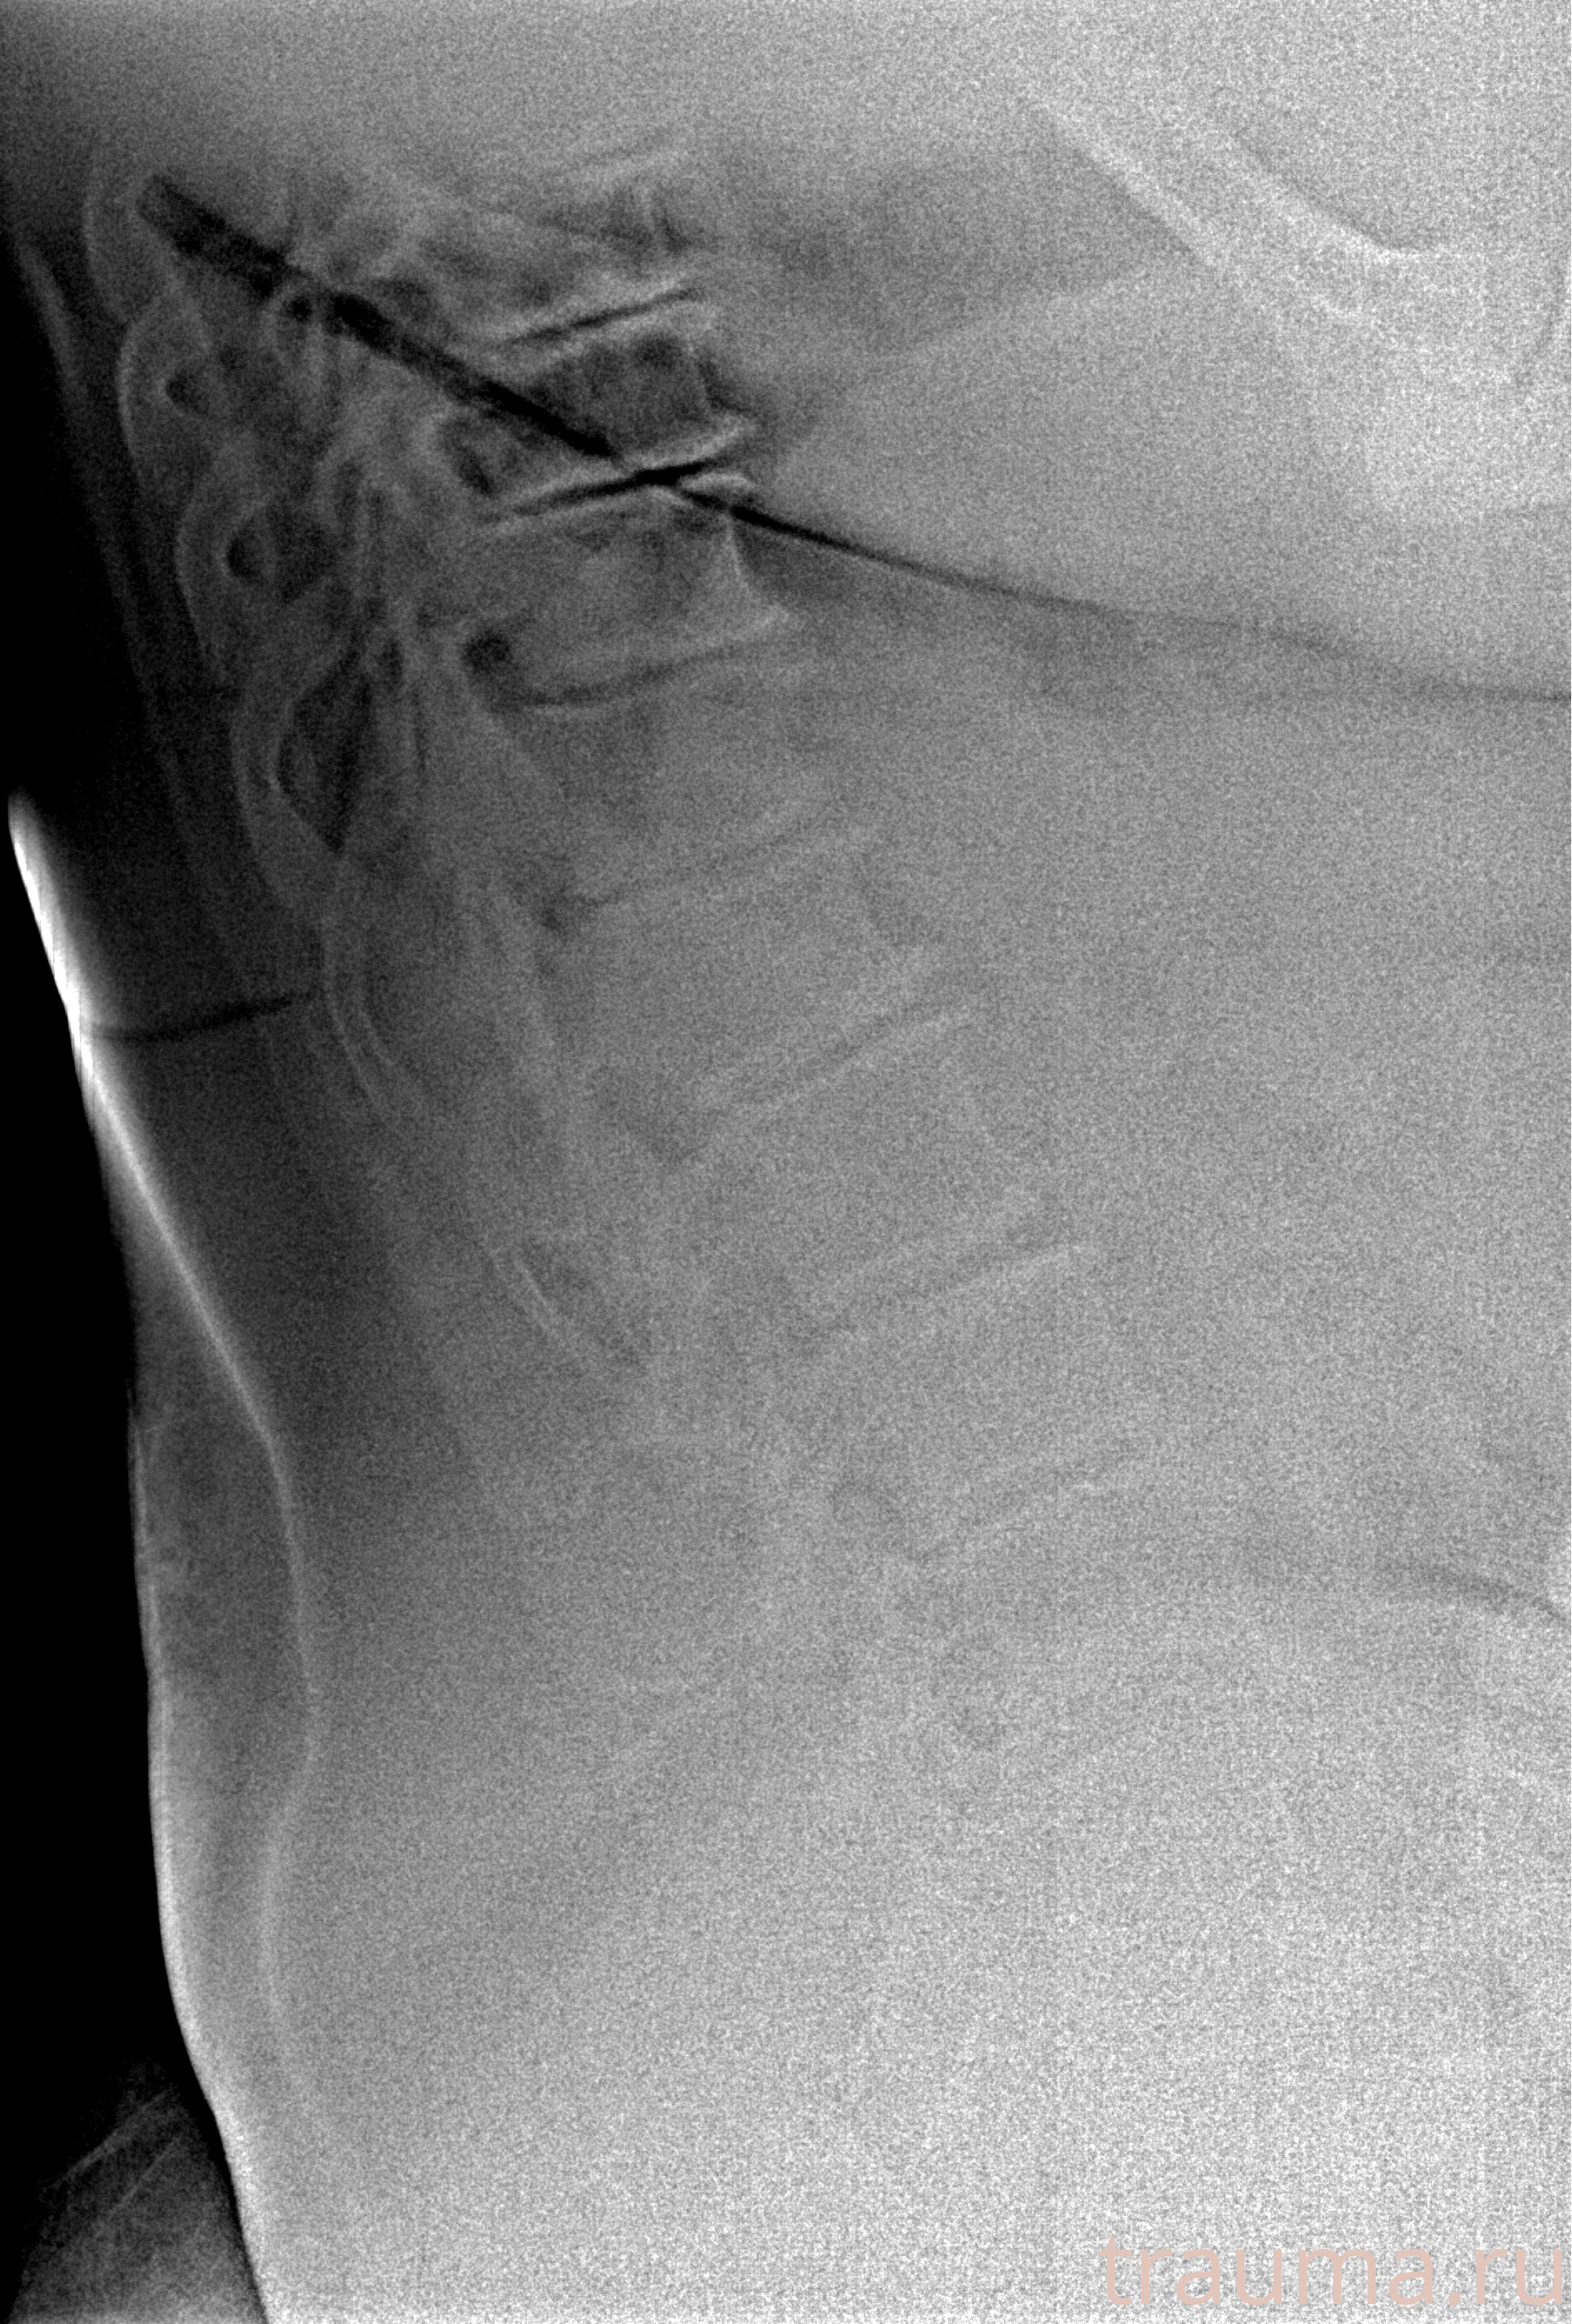

Рентгенограммы

Рентген на дому: по вашему адресу приезжает врач-рентгенолог, травматолог-ортопед с мобильным рентгеновским аппаратом, проводит диагностику травмы или заболевания, делает необходимые рентгенограммы, дает рекомендации по дальнейшему лечению. Получить качественные снимки в домашних условиях возможно благодаря уникальной методике, разработанной МосРентген Центром для института  Склифосовского